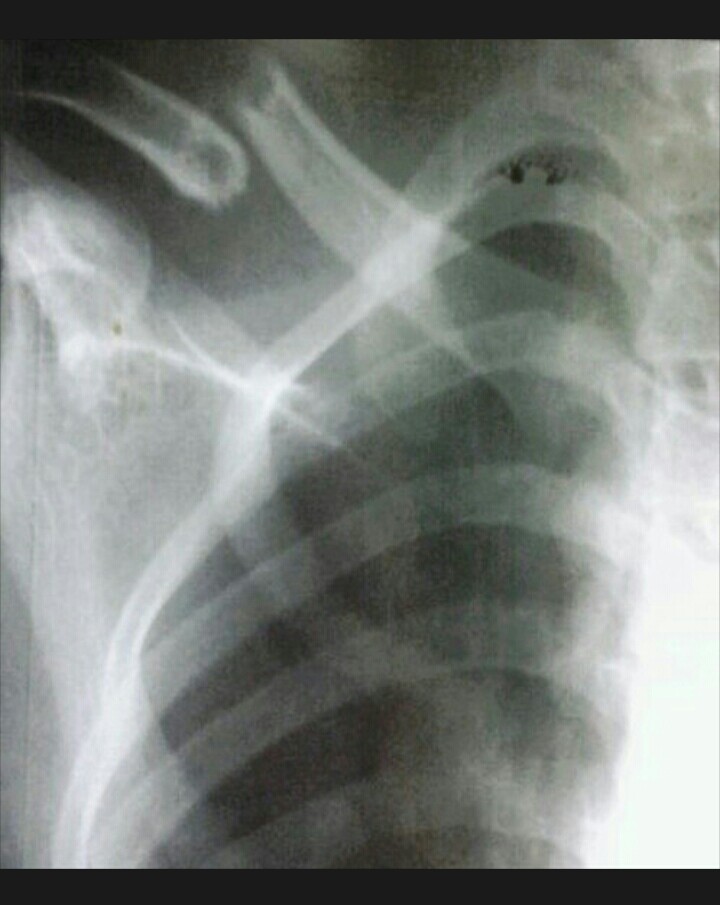

Patah Tulang Selangka

image

Patah tulang selangka (clavicle fracture) termasuk salah satu kasus patah tulang yang sering dijumpai. Secara epidemiologi jumlah kasusnya berkisar 4 % dari semua kasus patah tulang1.

Penanganan kasus patah tulang selangka berkembang dari masa ke masa. Dahulu patah tulang selangka (clavicle fracture ) ditangani secara konservatif2 Perkembangan implan tulang yang semakin pesat sejak berdirinya beitsgemeinschaft für Osteosynthesefragen di Jerman ikut memberikan pilihan lain. Reposisi secara terbuka kemudian melakukan fiksasi secara internal memberikan pilihan reposisi tulang yang lebih baik. Beragam metode fiksasi internal ini seperti dengan Kirsner wire, AO recon plate, Clavicular plate dan Hook plate untuk distal clavicle fracture.

Diluar pilihan operatif tersebut pilihan rasional untuk melakukan terapi konservatif kasus patah tulang selangka dengan Figure of Eight atau Ransel Verban. Pada beberapa penelitian menunjukkan hasil fungsional yang cukup baik dengan terapi konservatif, meskipun dengan waktu kesembuhan rerata yang lebih lama2.

Patah Tulang Selangka / Collarbone Fracture (Calvicular Fracture)

Patah tulang selangka (collarbone fracture/ clavicle fracture) termasuk salah satu kasus patah tulang yang sering dijumpai. Secara epidemiologi jumlah kasusnya berkisar 4 % dari semua kasus patah tulang1.

Penanganan kasus patah tulang selangka berkembang dari masa ke masa. Dahulu, patah tulang selangka (clavicle fracture ) ditangani secara konservatif2. Perkembangan implan tulang yang semakin pesat sejak berdirinya beitsgemeinschaft für Osteosynthesefragen di Jerman ikut menawarkan pilihan lain.

Reposisi secara terbuka kemudian melakukan fiksasi secara internal memberikan pilihan reposisi tulang yang lebih baik. Beragam metode fiksasi internal ini dilakukan seperti dengan Kirsner wire, AO recon plate, Clavicular plate dan Hook plate.

Diluar pilihan operatif tersebut pilihan lain untuk terapi secara konservatif pada kasus patah tulang selangka adalah dengan Figure of Eight atau Ransel Verban. Pada beberapa penelitian menunjukkan hasil fungsional yang cukup baik dengan terapi konservatif, meskipun dengan waktu kesembuhan rerata yang lebih lama2.